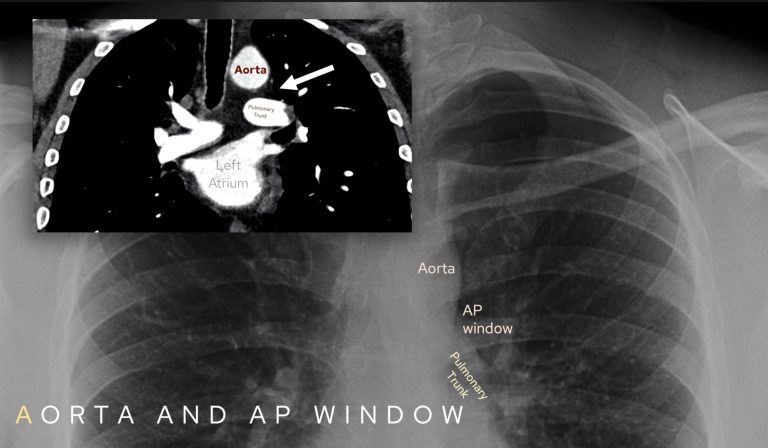

A: Aorta and aortopulmonary (AP) window

Confirm the aortic knuckle and AP window are well defined. The aortopulmonary or AP window represents the small concavity between the aorta and pulmonary trunk. You should see this on every chest X-Ray you look at and you may need to look ‘through’ the aorta to see it when the aorta is tortuous.

A convex or opaque AP window is concerning for nodal disease or lung cancer. I have seen films where this is the only abnormality so look carefully!

Loss of aortic contour may indicate a tumour or in the acute setting could mean dissection or traumatic aortic injury.

Ensure you review the aortic knuckle and aortopulmonary window on each film you look at: there should be a concavity between the aorta and pulmonary trunk.